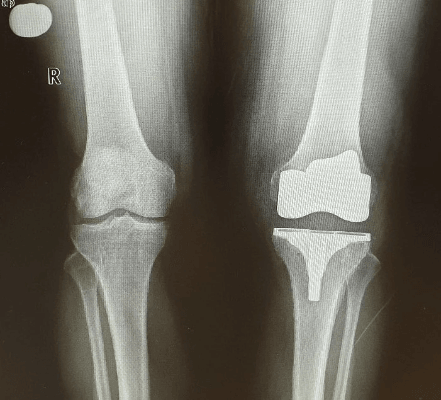

KNEE REPLACEMENT SURGERY

Our advanced knee prosthesis surgery team uses the latest techniques and most durable implants that allow a very high percentage of prompt recovery of normal activities, with unimaginable prosthesis longevity.

Advanced Knee Prostheses

Designed to correct any degree of deformity depending on the severity of osteoarthritis. Disappearance of pain and recovery of normal walking.